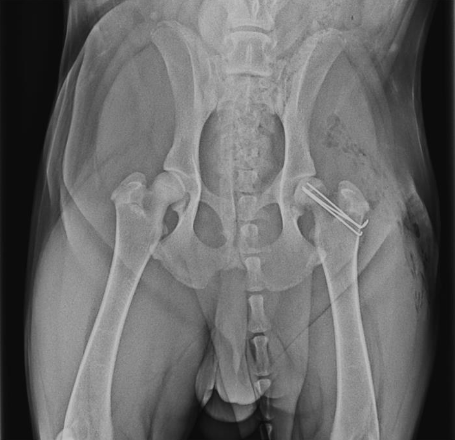

OFA (left) and PennHIP (right) radiographs on the same canine patient. The hips look reasonable on the OFA images (left) but the extreme laxity is readily evident on the PennHIP radiographs.

The most common radiographs made to evaluate dog hips are the traditional, “legs extended” view. These are also the type of radiographs that are reviewed by the Orthopedic Foundation for Animals (OFA) for grading. These radiographs are good, but imperfect. If these pelvic radiographs show a deformed hip, very loose hip, or an arthritic hip, one can confidently conclude that the dog hip is dysplastic. However, if the canine’s hips look good on these OFA radiographs, particularly in a puppy, there may still be laxity that just cannot be seen with these radiographs. That explains why OFA will not provide a grade on a dog’s hips prior to 2 years of age (unless the hips are obviously abnormal). This is due to the fact that these Orthopedic Foundation for Animals (OFA) style radiographs do not show hip looseness (laxity). As mentioned above, hip laxity is the first characteristic of hip dysplasia. Therefore, if the legs extended radiographs look very good, veterinary surgeons really want to know how lax (loose) the hips are. To know how loose the dog hips are, a veterinarian needs to take distraction radiographs.

Distraction radiographs, of which PennHIP radiographs are the most extensively studied and used, involve the physical distraction of the hips at the time of taking the X-ray to see how loose the dog hips are. From these PennHIP radiographs, the looseness is actually measured (called the distraction index; DI), not just subjectively estimated, and compared to the DI of many other dogs of only the same breed. With this information, a prediction is made as to the risk (ie probability) that your dog will develop hip osteoarthritis. These PennHIP distraction radiographs are most pertinent in assessing hips in young dogs that look good on the legs extended views. Knowing how loose those canine hips are, and the associated risk of developing osteoarthritis, can inform decisions on breeding that dog or on doing prophylactic surgeries to try and prevent the development of OA (see next).